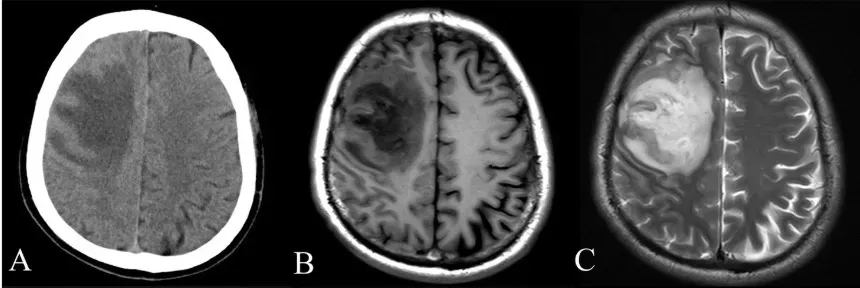

Humans have been asking why there is a felt inner world for as long as they have written anything down, but only in the last few decades have we been able to watch the living brain in real time. Early thinkers framed consciousness in terms of souls, spirits, or vital essences, because there were no tools to peek inside a working skull. The turning point came with technologies like functional MRI and high-density EEG, which let scientists observe chains of brain activity unfolding as people make decisions, recall memories, or become aware of a sound. Suddenly, questions that once lived only in philosophy seminars moved into the lab, with testable predictions and data.

Researchers have since mapped distinct patterns linked to different states of consciousness: wakefulness, deep sleep, anesthesia, coma, and psychedelic states. In wakeful awareness, brain regions in the frontal and parietal lobes often form tightly connected networks, allowing information to be flexibly shared and integrated. Under deep anesthesia or in some coma patients, that rich integration collapses into more isolated, repetitive activity. This shift from dynamic, globally coordinated activity to local, rigid patterns is now a central clue in many scientific theories of consciousness. The brain, it seems, must strike a delicate balance between order and chaos to sustain the feeling of being a self in a world.

The stakes of understanding consciousness are not just philosophical; they show up in hospital rooms, courtrooms, and engineering labs. In intensive care units, doctors must decide whether patients who cannot speak or move have any residual awareness. Brain imaging studies have revealed that some people diagnosed as vegetative can still follow commands in their mind, activating different brain areas when asked to imagine playing tennis or walking through their house. Recognizing this hidden consciousness can dramatically change how families and clinicians approach care, pain management, and the ethics of life support decisions. A better science of consciousness could reduce the risk of quietly misclassifying aware people as irreversibly gone.